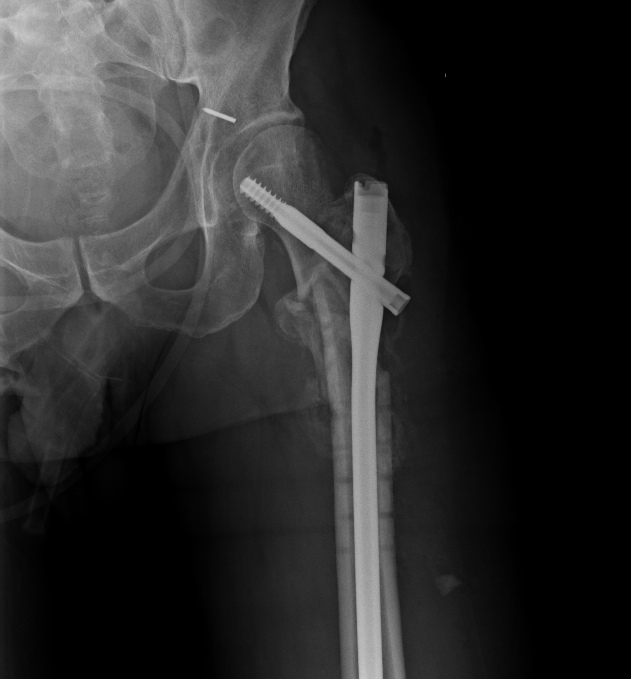

Удалили  DHS, пришлось вытащить единым блоком, винт прокручивался. . Опознавательных знаков на имплантате не обнаружили. Дополнительный винт был введен во фрагмент, который оказался не связан ни с чем, так что удалили и его После удаления была хорошая подвижность. Сделали остеосинтез вот так. Комментарии и критика приветствуются.